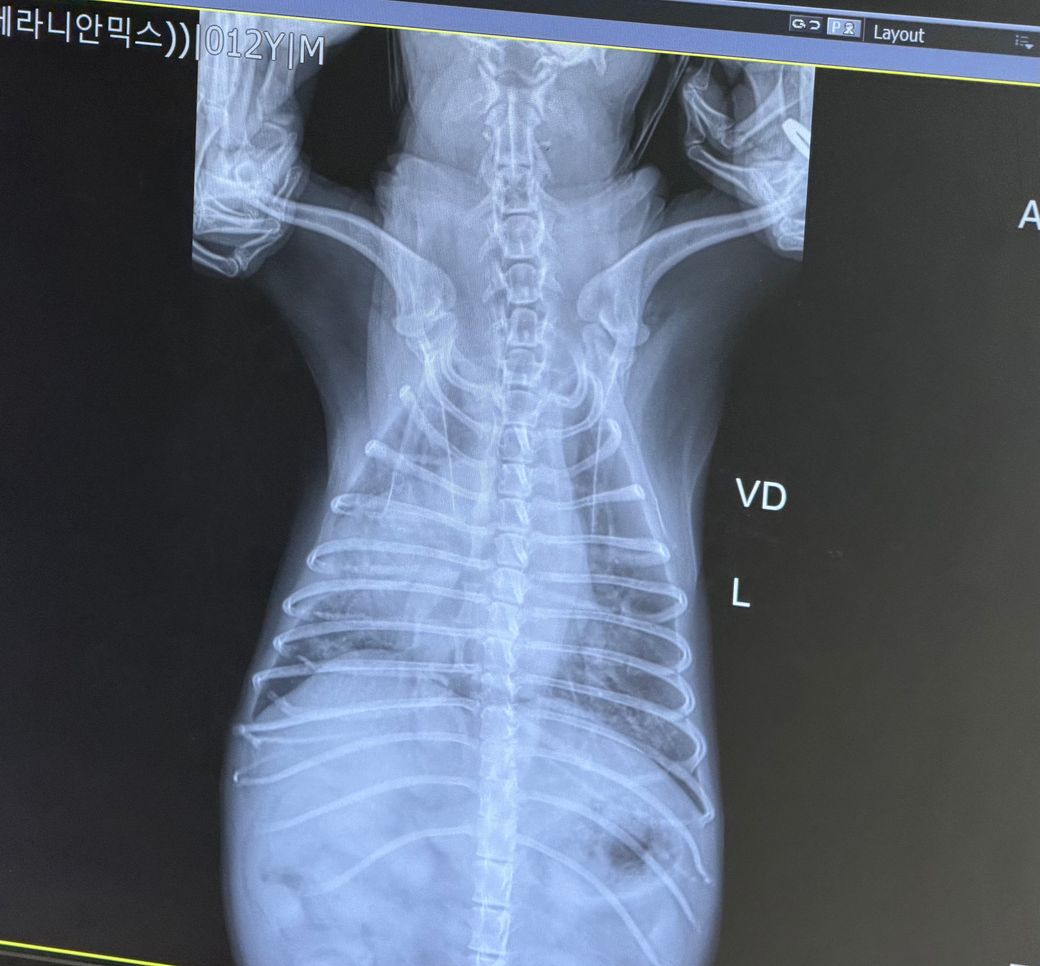

2차 병원 흉부 X-ray 결과:

• 왼쪽 폐 중간~하부 폐엽에 국소적 침윤

• 오른쪽 폐는 비교적 정상

• 양측 대칭성 소견은 아님

복배상 폐 우측 중엽의 경화상이 관찰되는 상태이며 심장의 변위 양상이 관찰되지 않습니다.

흉수가 소량 동반되어 있으나 폐 전엽의 뒤쪽 변연의 방향, 폐 중엽의 뒤쪽 변연 주행 방향을 볼때 폐 염전으로 볼 근거는 부족하며

심장의 크기 증가 및 흉골 접합면적 증가, 좌심방 돌출 양상이 동반되며 복배상 폐후엽의 침윤 양상이 동반되어 관찰되는 상태로 심인성 폐수종을 고려해야 하는 소견입니다.

하지만 우측 폐 중엽의 경화상의 감별진단 항목은

1. 오연성폐렴(흡인성과는 다릅니다.)

2. 상부 호흡기계 질환의 하부 호흡기계 유주에 의한 이차적인 폐렴

3. 개 인플루엔자

이렇게 3가지가 유효하며 현상태에서는 1번 가능성이 가장 높아보입니다.